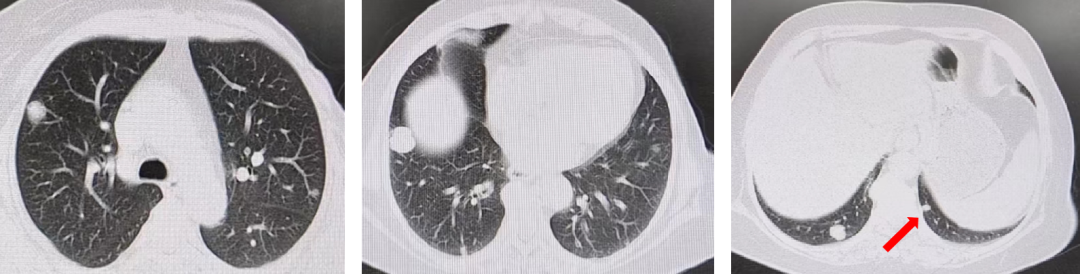

胸部+全腹部增强CT(我院 2021-02-17):直肠壁增厚,考虑直肠癌;盆腔多发稍大淋巴结;肝左叶低密度影,不除外转移瘤;双肺多发结节影,考虑转移瘤(左肺3个,右肺6个,较大者位于右肺下叶,直径约1.6cm)。

盆腔+上腹部增强MRI(我院 2021-02-20):肝左叶异常信号,考虑转移;双肺多发结节影。

CT引导下肺结节穿刺活检(2021-02-18):坏死组织中可见异型腺体,考虑腺癌。免疫组化结果(2021-02-24):AE1/AE3(+),TTF-1(-),CDX2(+),NapsinA(-),CK20(+)。

KRAS、NRAS、BRAF基因检测:KRAS 2号外显子G12X突变。MLH1(+),PMS2(+),MSH2(+),MSH6(+),HER2(0)。